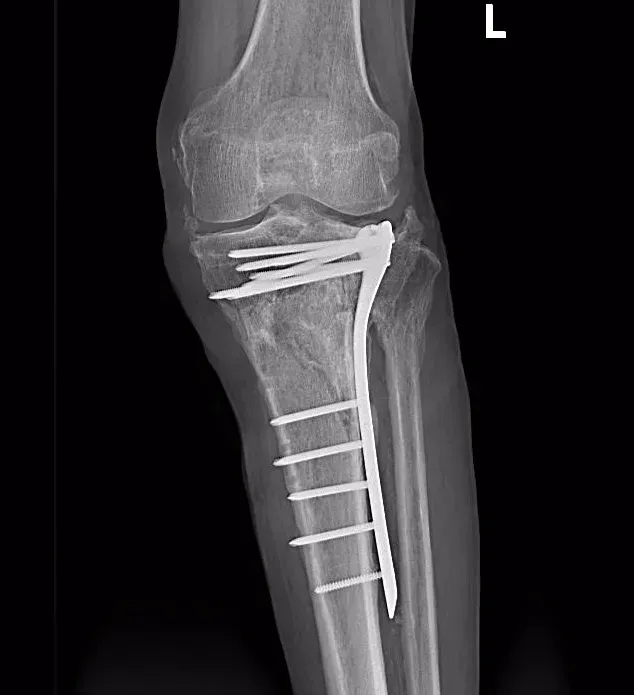

术前

术后